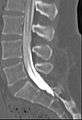

Myelogram showing arachnoiditis in the lumbar spine. | |

Myelography is a type of radiographic examination that uses a contrast medium to detect pathology of the spinal cord, including the location of a spinal cord injury, cysts, and tumors. The procedure often involves injection of contrast medium into the cervical or lumbar spine, followed by several X-ray projections. A myelogram may help to find the cause of pain not found by an MRI or CT.